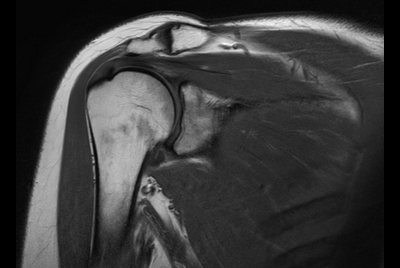

Push-button Shoulder exam, under 5 minutes